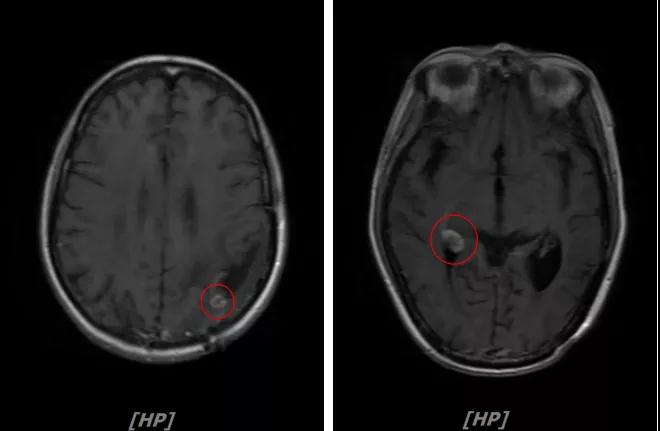

5. 病情第4次进展:2019年11月患者出现视野模糊等症状

头颅增强MR:左侧顶颞叶见片状T1WI低信号、T2WI高信号影,病灶大部信号接近脑脊液,增强后术区边缘左侧顶叶见结节状强化影,大小约10x8x11mm,较2019-03- 15MR老片大致相仿;右侧脑室三角区见结节样T1WI等低信号、T2WI不均匀稍高信号影,增强后不均匀明显强化,大小约24x18x20mm,较2019-03-15MR老片明显增大;两侧半卵圆区、侧脑室旁见较对称片状T1WI低信号、T2WI高信号影,增强后未见明显强化,较前片相仿;余脑室、脑池、脑沟大小形态可,中线结构向左偏移。

左顶颞叶转移瘤治疗后改变

右侧脑室三角区旁强化结节,较2019-03-15MR老片明显增大 左侧顶叶强化结节,较2019-03-15MR老片大致相仿

两侧脑室旁云絮状异常信号,考虑放疗后改变

患者三线治疗的PFS为14个月,2019年12月给四线治疗为“吡咯替尼+阿那曲唑”基础上联合曲妥珠单抗。

患者视野模糊等症状有所改善,继续定期复查。